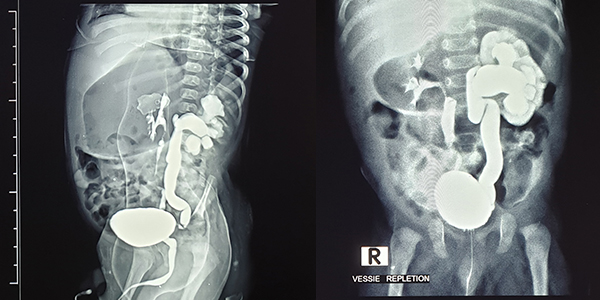

هل يجب إجراء تصوير (Échographie) من أجل التشخيص؟

ليس من الضروري إجراء تصوير طبي لتشخيص التهاب الحويضة والكلية الحاد (Pyélonéphrite aiguë)، إلا أن التصوير قد يكون مفيدًا في بعض الحالات الصعبة أو الغامضة.

أما المناطق منخفضة الصدى (Hypoéchogènes) فهي أقل شيوعًا، وقد تدل على احتمال تكون قيح (Abcès) في الكلية.

وفي بعض الحالات المضللة، قد تُظهر الموجات فوق الصوتية لالتهاب الحويضة والكلية الحاد ما يشبه وجود كتلة داخل الكلية (Masse intrarénale)، مما يستدعي تفسير النتائج بحذر وربطها مع الأعراض السريرية والفحوصات المخبرية.

تعدّ الموجات فوق الصوتية للكلية (Échographie rénale) مفيدة بشكل خاص لاكتشاف أي تشوّه خلقي في المسالك البولية، إذ إن وجود مثل هذه التشوهات يزيد من خطر الإصابة بعدوى المسالك البولية.

ويُفضَّل أن تبدأ فحوصات الكشف عن التشوهات الكلوية بالموجات فوق الصوتية، بعد فترة من انتهاء نوبة العدوى، لضمان دقة النتائج وتجنّب تأثير الالتهاب الحالي على الصورة التشخيصية.